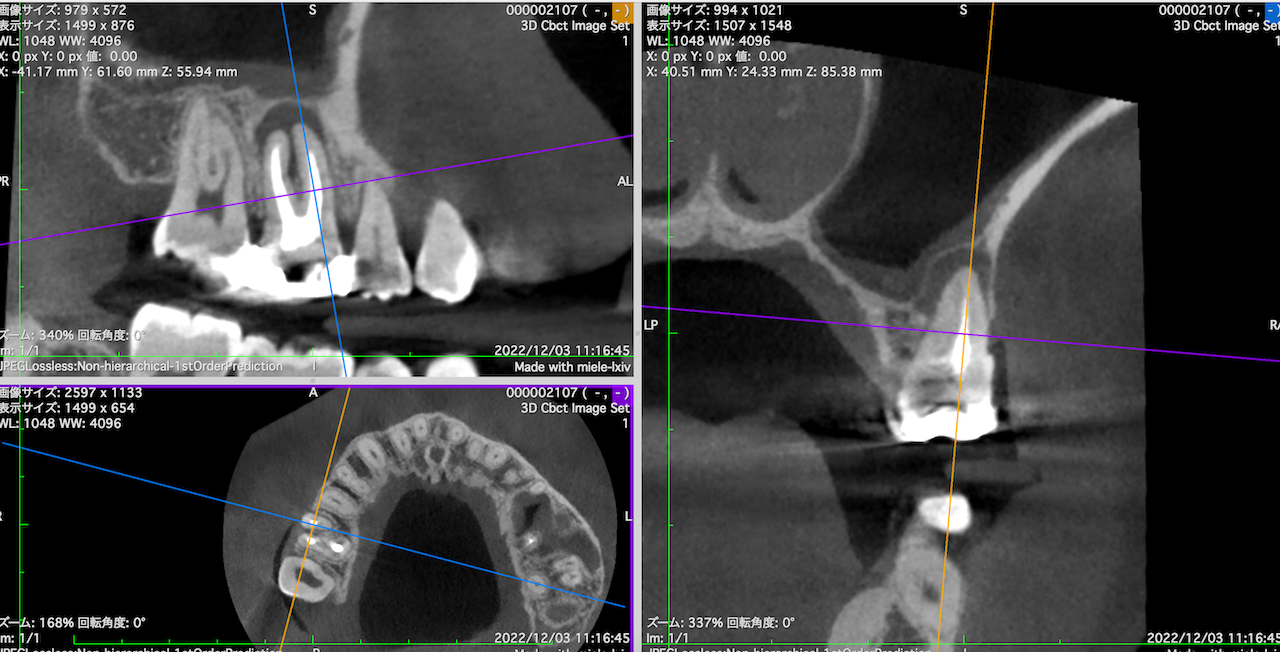

この流れで計測すると以下のようになる。

#3 MB

#3 DB

MBとDBは近接し、3mmで切断した際の頬舌的な厚みも3.5~4mmだ。

そしてMB1, MB2は近接している。

またMBもDBも近接している。

以上のことからこのApicoectomyは容易であると私にはわかる。